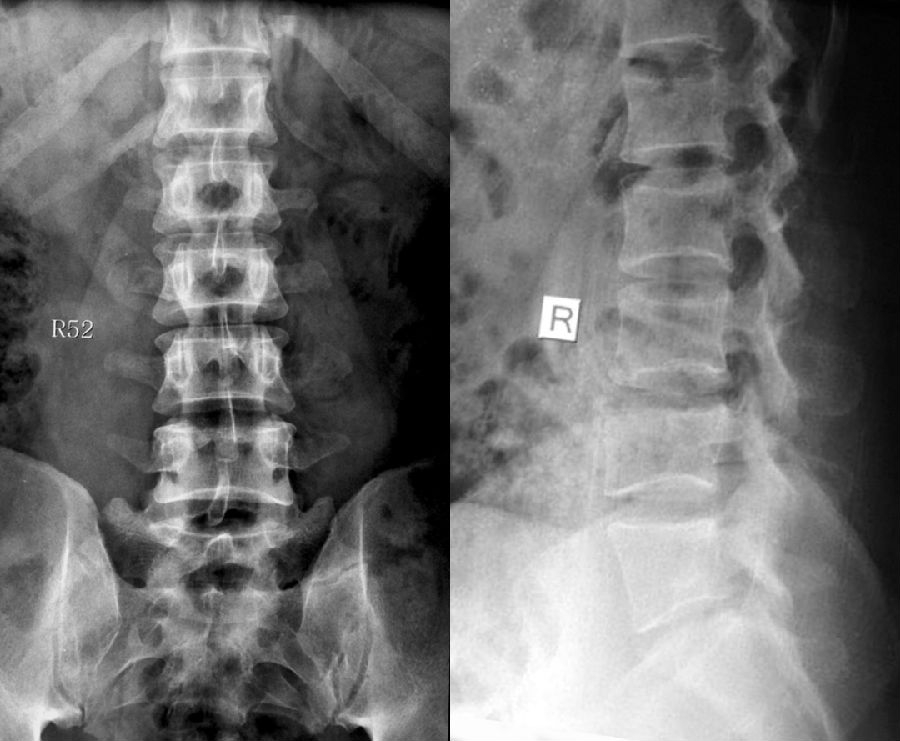

1984年,Castellvi提出LSTV分类系统将移行椎分为Ⅰ-Ⅳ型。

Ia型(单侧)和Ib型(双侧):横突肥大宽度超过19mm

IIa型(单侧)和IIb型(双侧):横突与骶骨相接触形成假关节

目前,腰骶移行椎以Castellvi的分类方法最为常用。其主要根据横突形态及其与骶骨、髂骨是否融合或形成假关节而分为4型,Ⅰ、Ⅱ、Ⅲ型又根据单、双侧分为A、B两个亚型。

正常

I型:主要为腰5横突发育不良,横突宽度大于19mm,并将其分为两个亚型Ia(单侧横突发育不良)或Ib(双侧横突发育不良)

L5右侧横突肥大,为Ⅰa型

L5双侧横突肥大,为Ⅰb型

II型:表现为不完全的腰椎骶化,具有增宽的横突,并且和骶骨形成假关节,并将其分为两个亚型IIa(单侧关节形成)或IIb(双侧关节形成)

L5左侧横突肥大,假关节形成,为Ⅱa型

L5双侧横突肥大,假关节形成,为Ⅱb型